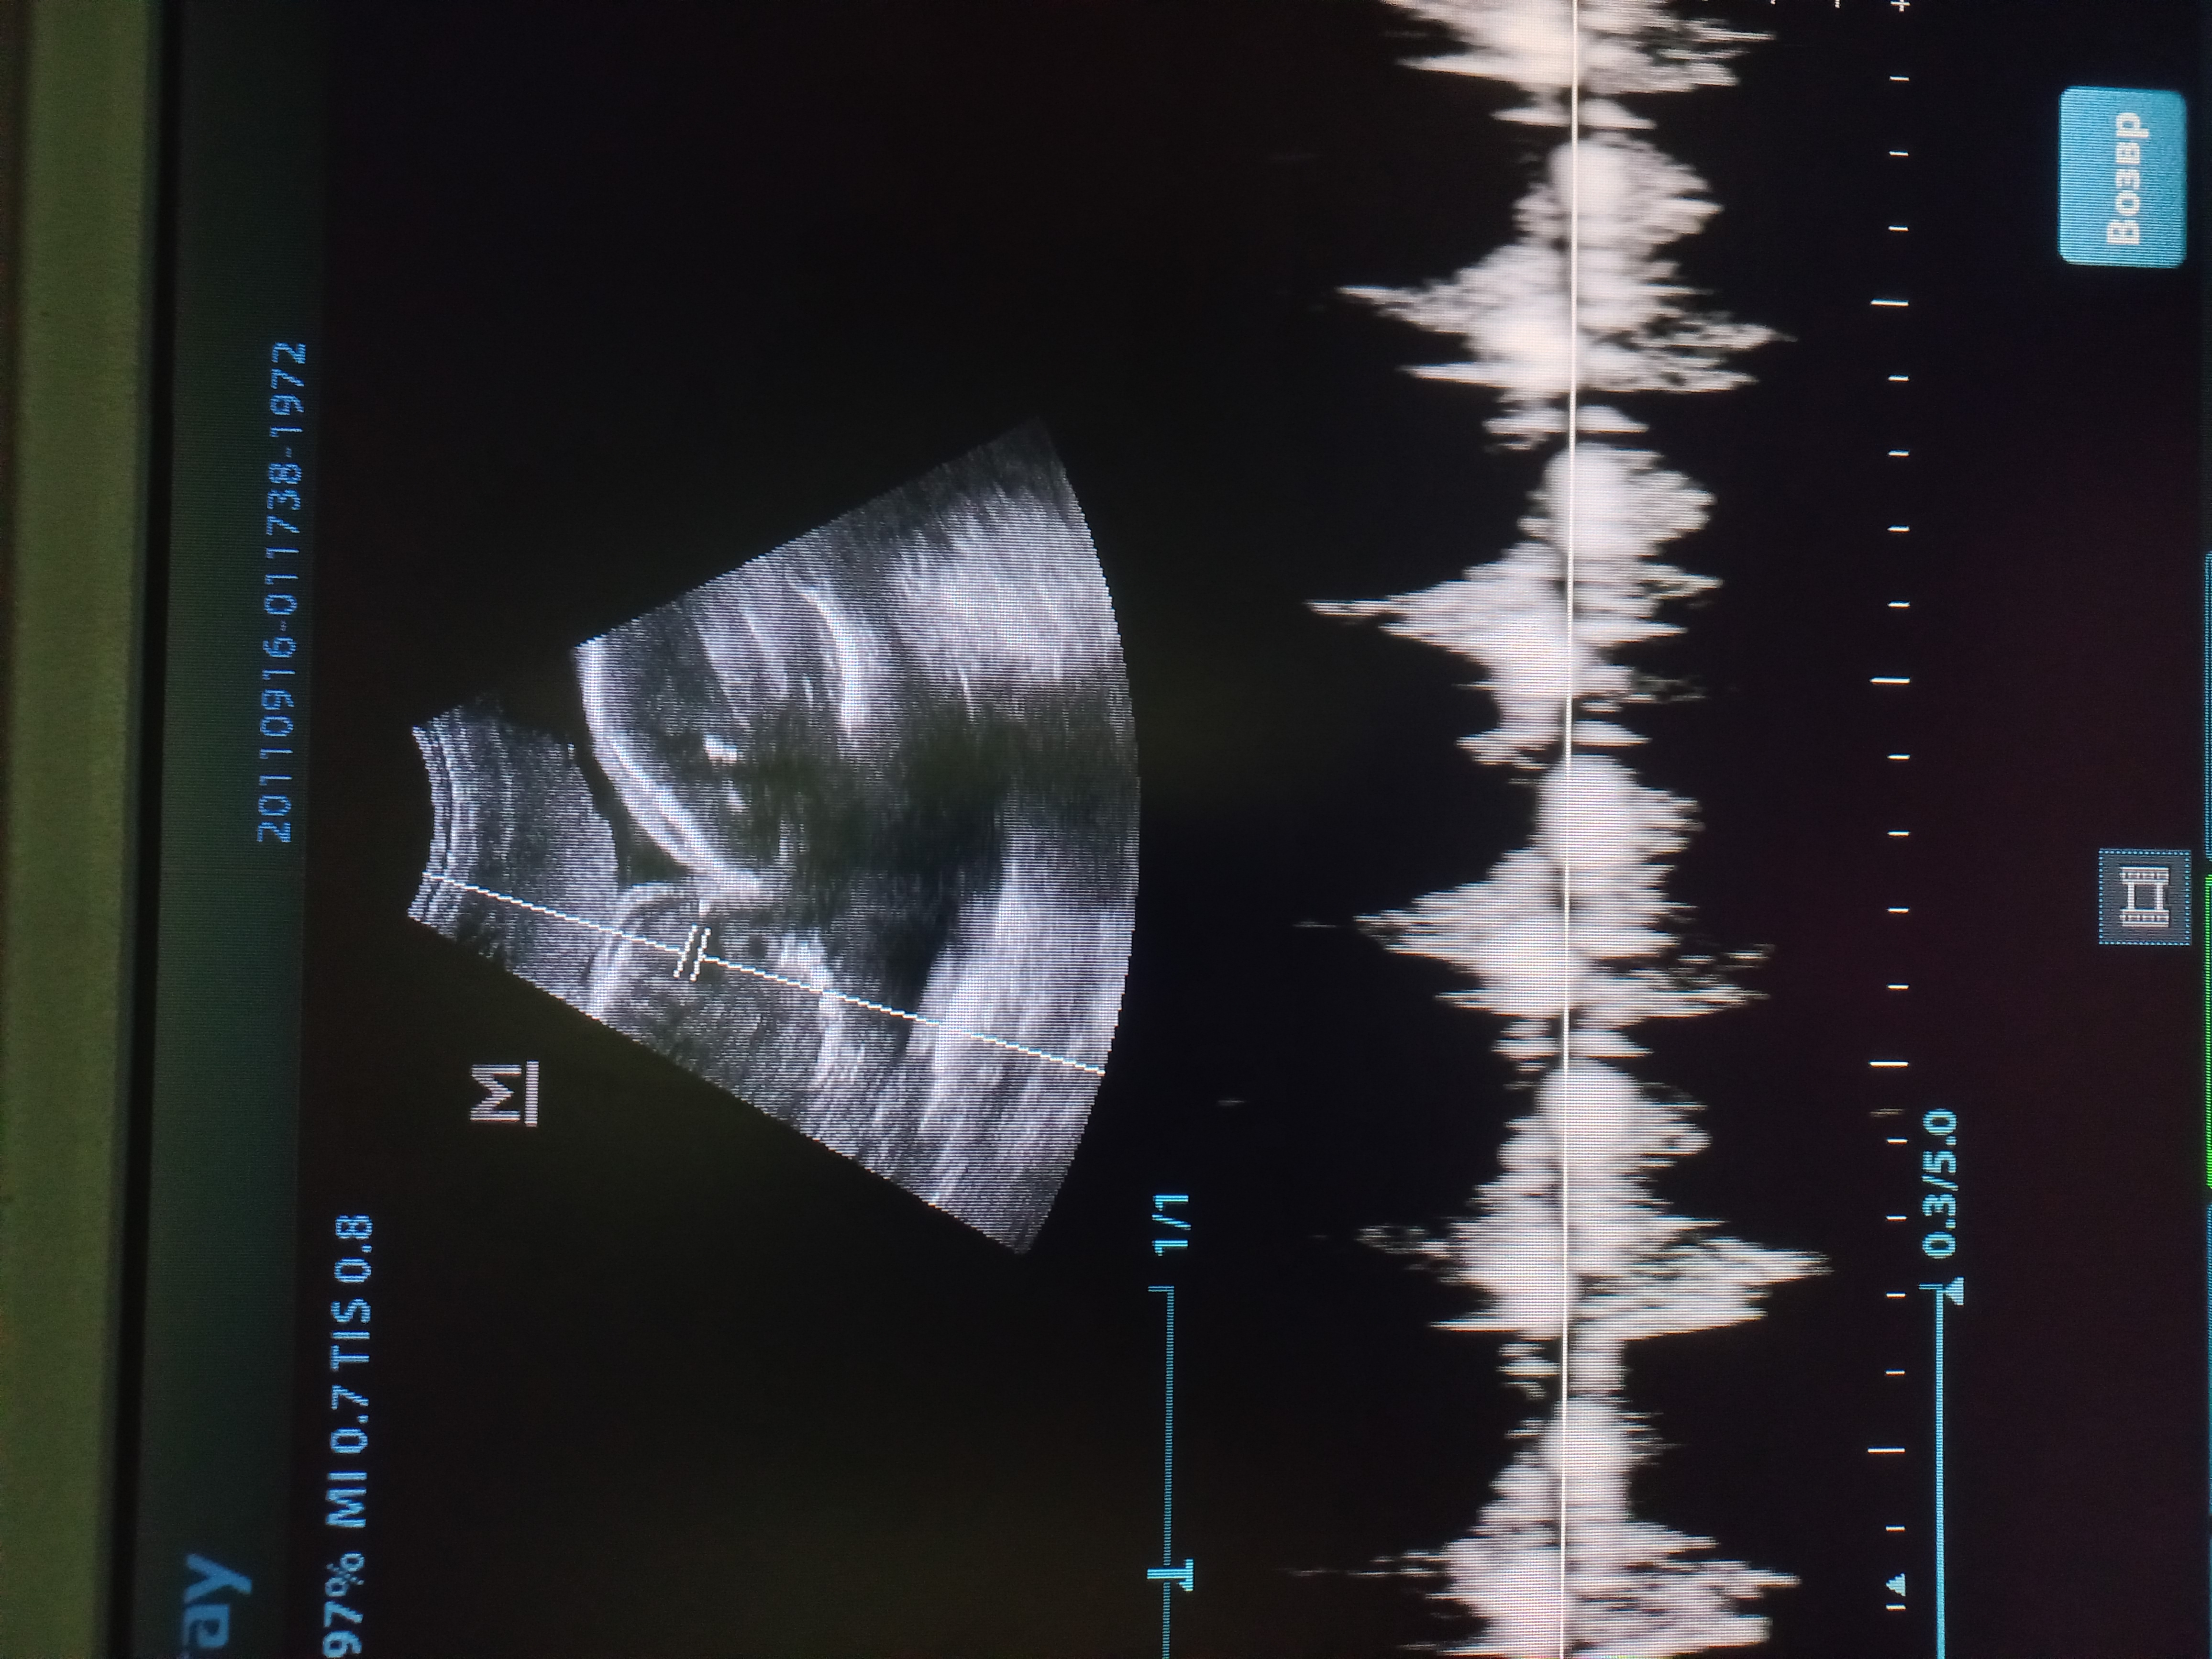

В участковую ветеринарную лечебницу ОГУ «Саратовская межрайСББЖ» обратилась хозяйка континентального той-спаниеля (папийон) с жалобой на отсутствие родовой деятельности у ее собаки. Течение беременности шло без осложнений, собака наблюдалась с момента течки. В полости матки находилось 4 щенка. У одного из щенков 8.12.2025 года при УЗИ выявили брадикардию (142 уд/мин). Было принято решение о срочном кесарево сечении.